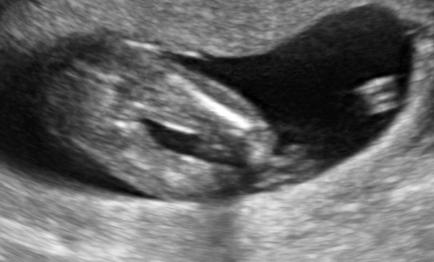

Zdravim chcem sa spytat vedeli by ste niekto rozoznať pohlavie dietata v 16tt pošlem fotku aj video z 3d povedali mi ze na 75% je to dievčatko no neviem. Pište odpoveď DAKUJEM

@prskavka2223 nam sa potvrdilo dievca a ano vidim tam to kavove zrnko, tak najskor to dievcatko